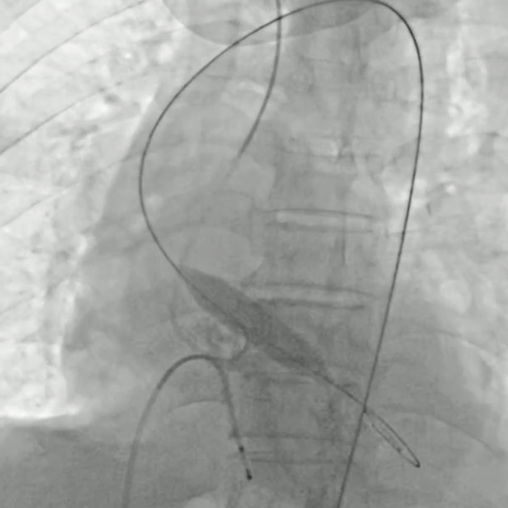

手术中经右股动脉入路,拟植入VenusA-L 29mm瓣膜。因弓部角度锐利,导丝跨弓两次尝试后成功,造影未见主动脉夹层。最终在超声引导下回收重置,瓣膜同轴性理想,展开良好,反流完全消失,手术顺利完成。

超声引导确认植入深度

回收后再次释放, 瓣膜植入同轴性良好,展开充分,反流消失, 手术顺利完成